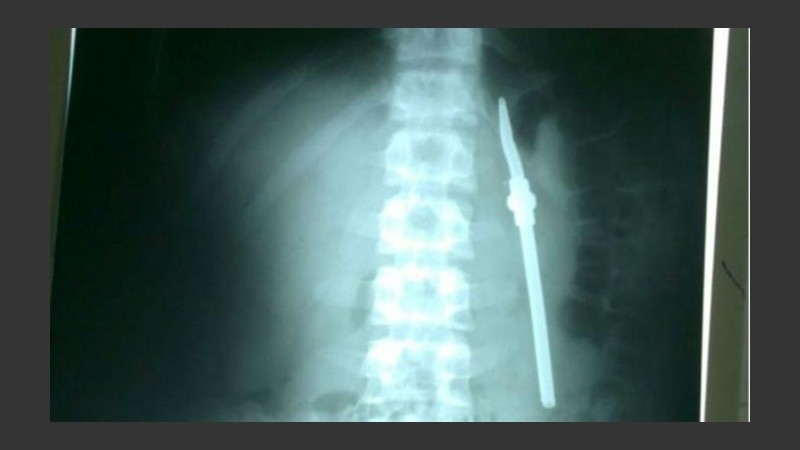

Un detenido de 19 años, que ingresó a una cárcel de Paraná hace dos semanas, protagonizó un extraño hecho el pasado jueves. Mientras tomaba mate a la madrugada se tragó la bombilla.

Según apuntó Minutouno, el delincuente fue preso acusado por robo y tentativa de homicidio. Tras ingerir el sorbete metálico fue derivado al Hospital San Martín, donde se le detectó el elemento.

El ladrón fue operado y se le sacó la bombilla. El parte médico indicó que su evolución es favorable y que podría volver a la cárcel en cuestión de días.